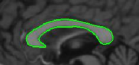

5.3 Elliptical templates

Many of the bio-medical cells can be approximated with an ellipse [14]. We present results using two elliptical shaped templates: a spline synthesized ellipse for which we use the partial derivatives given in equations (36) and (41) directly, an exact ellipse for which we use the parameterization given in [16] and use the equation (26). First row of Figure 8 corresponds to a hand drawn ellipse and the second row correspond to a parametric ellipse. We considered these two parameterizations to show that the algorithm performance is not critically dependent on the parameterization. These are fundus images taken from [32]. The presence of veins in the fundus anatomy obscures snakes whose energies rely on image derivative functions. From the results shown in Figure 8, we infer that the proposed technique is less affected by the vein structures or the parameterization and captures the near elliptical shape of the fundus outline.